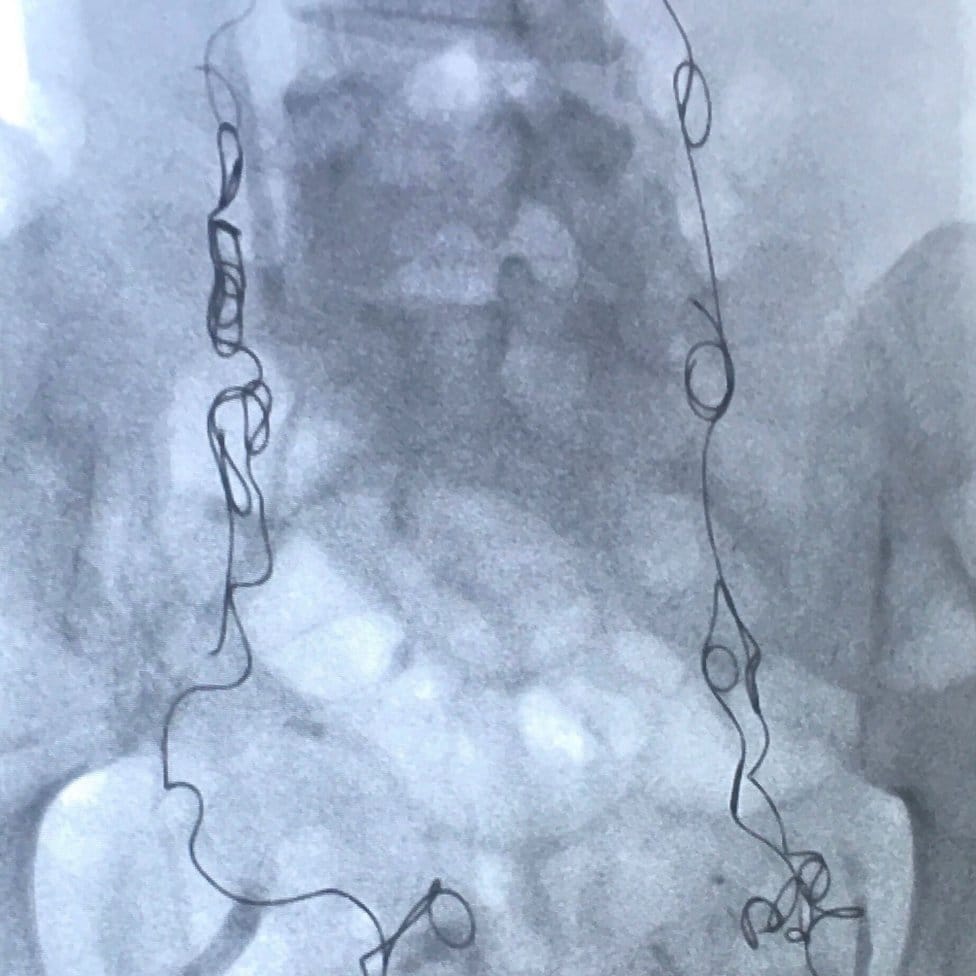

Utorak je, 14. avgust 2018. godine, a ja sam pod anestetikom, ležim na operativnom stolu, dok se metalni kalemi ubacuju u moje vene jajnika i karlice preko katetera u mom vratu.

Nedavno mi je postavljena dijagnoza pelvičnog kongestivnog sindroma (PKS), ili refluksa vene jajnika, kako je još poznat, stanje koje može da izazove nagomilavanje krvi u venama jajnika i karlice, od koje se one šire i počinju da pritiskaju okolne organe.

Nema garancija da će zahvat kojem se podvrgavam, poznat kao embolizacija vene, funkcionisati.

Ali rečeno mi je da u oko 80 odsto slučajeva ona uspeva da smanji ili potpuno ukloni simptome, tako da deluje kao moja najbolja opcija posle više meseci neprekidnog bola.

Ako to ne funkcioniše, opcija je emobolizacija karlične vene, u kojoj je vene zapečate i blokiraju.

On je potvrdio da imam pelvički kongestivni sindrom u levim i desnim venama jajnika i u delovima druge vene u mojoj karlici, bočnoj veni.

Emobilizacija koju sam imala 2. avgusta 2018. godine blokirala je moje zakrčene vene metalnim kalemima da ne mogu više da se pune krvlju, uvećavaju i nanose mi bol.